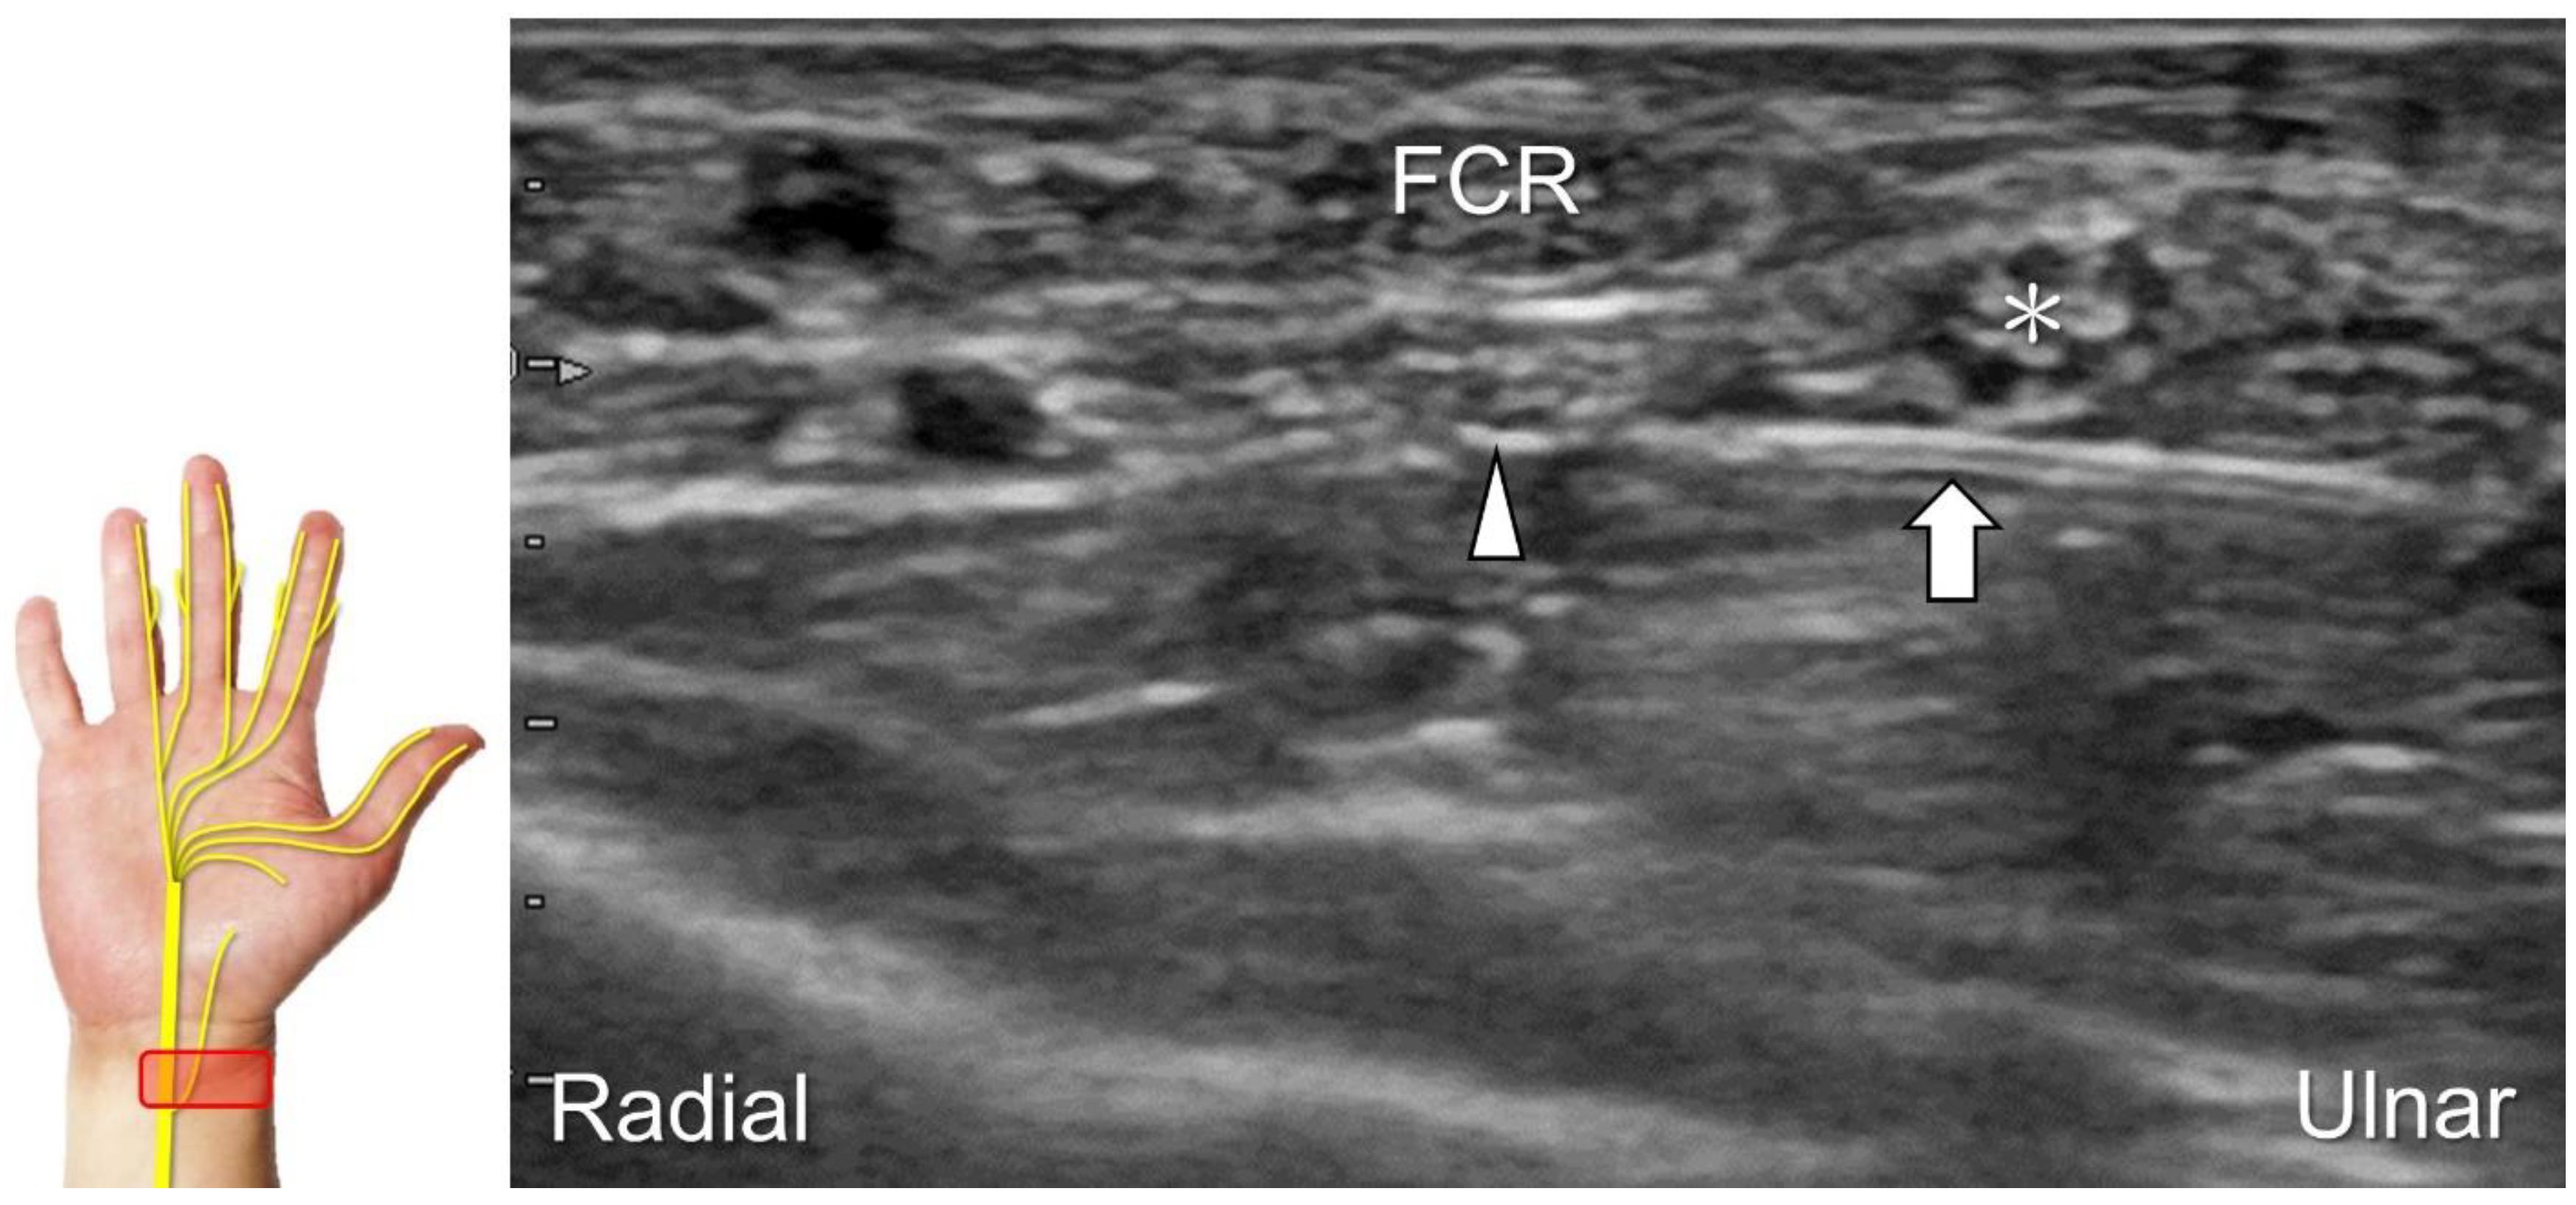

Clinical Implication

The recurrent motor branch may be injured during carpal tunnel release, trigger point injection of the thenar muscle, and repetitive impact of the thenar eminence [34]. In the case of nerve injury, the thenar muscle is likely to undergo atrophy, leading to a subsequent reduction in pinch and grasp forces. US reveals a swollen fascicle and an indistinct border of the injured nerve, with poor visualization of the epineurium (Figure 12; Video S3). US-guided hydrodissection in short-axis view has been reported helpful for reducing thenar pain in a case with recurrent motor branch entrapment [36].

Figure 12. Sonographic imaging (short-axis view) shows the segment (A) distal to the neuroma of the recurrent motor branch of the median nerve (B) and the proximal segment (C). Asterisk: median nerve; white arrowhead: recurrent motor branch of the median nerve; black arrowheads: neuroma. FPB: flexor pollicis brevis muscle; AbP: abductor pollicis brevis muscle.